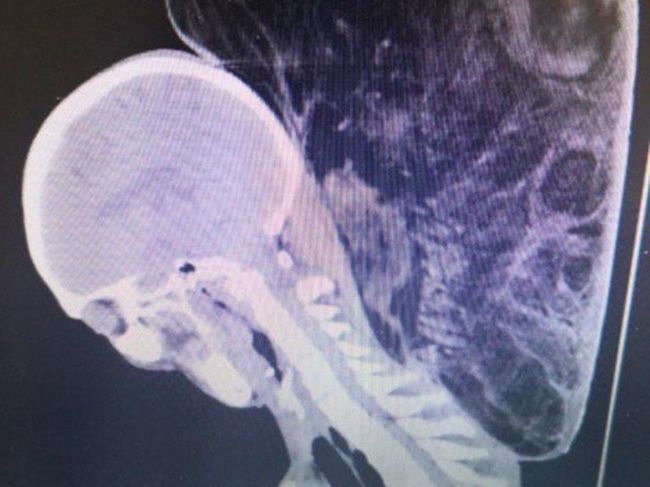

gif_animation 今月10日、ロシアの都市クルスクにて、”女性にしか見えない” 25歳のトランスジェンダーが27歳の男と街で知り合い、飲酒後、そのまま男の自宅へ。情報によると男はセックス中トランスジェンダーの首を絞め殺害、その後(動機は不明だが)遺体をバラバラにしたとの事。男の画像+トランスジェンダーの生前 → 死後の画像。[4]images